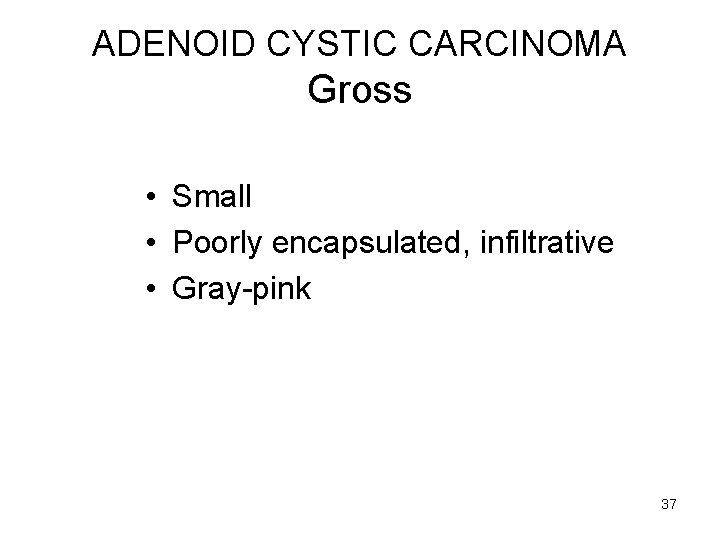

ADENOID CYSTIC CARCINOMA Gross • Small • Poorly encapsulated, infiltrative • Gray-pink 37